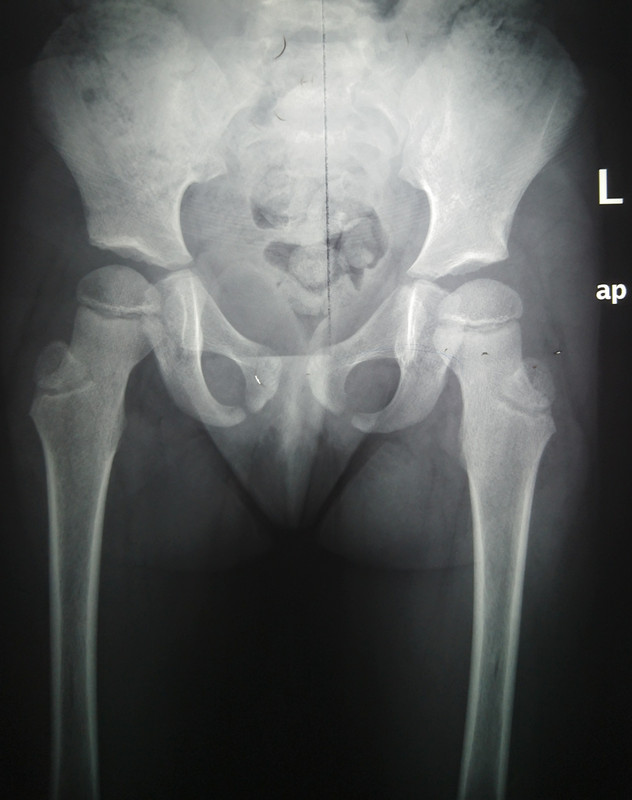

Рентген ТБС: Нормальные показатели

Раздел: Необычные решения